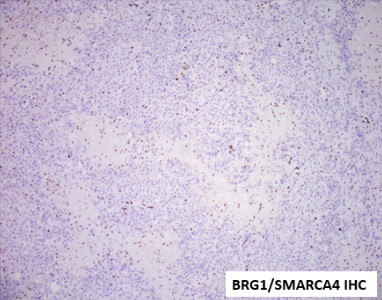

18 year-old female with 2 weeks of pelvic pain. CT showed a heterogeneous pelvic mass measuring 12.8 x 11.1 cm.CA-125 was 129 and AFP and beta-hCG (UPT negative) were not measured. She underwent right salpingo-oophorectomy. The ovary/mass measures 16.5 x 12 x 9.6 cm. Serially sectioning reveals a solid and partially cystic (90% solid, 10% cystic), variegated, homogenous, soft mass with punctate areas of hemorrhage. The fallopian tube grossly was not involved. Right external iliac and periaortic lymph nodes were involved by tumor. See below for the gross and microscopic photos of the ovary. The tumor cells show focal immunoreactivity for Pankeratin cocktail, AE1, AE3, Cam5.2 and 34BE12, patchy dot-like positivity with EMA, patchy and strong immunoreactivity for WT1 and SALL4, patchy immunoreactivity for Synaptophysin, focal positivity for Calretinin and CD10. Chromogranin and CD56, PAX8, OCT3/4, CD30, Inhibin, SF1, CD45, Desmin, GFAP and Sox10 were all negative in the tumor cells. INI1 expression was retained. What is the diagnosis?

Tumor cells grow in sheets, nests, cords, and trabeculae. Scattered follicle like spaces with eosinophilic or basophilic secretions are often seen. Cells have monomorphic round, ovoid or occasionally spindles nuclei with vesicular chromatin, small nucleoli, scant cytoplasm, and brisk mitotic activity. Large cells are present in half of these tumors, which are designated “small cell carcinoma, large cell variant” if the large cells are predominant. Immunohistochemistry reveals absence of SMARCA4 (and SMARCA2) in almost all tumors, along with diffuse expression of WT1, p53, and p16 and variable expression of claudin-4, SALL4, keratins, EMA (especially in the large cell component), CD10, calretinin, and all neuroendocrine markers. Inhibin and TTF1 are negative. Prognosis is poor.